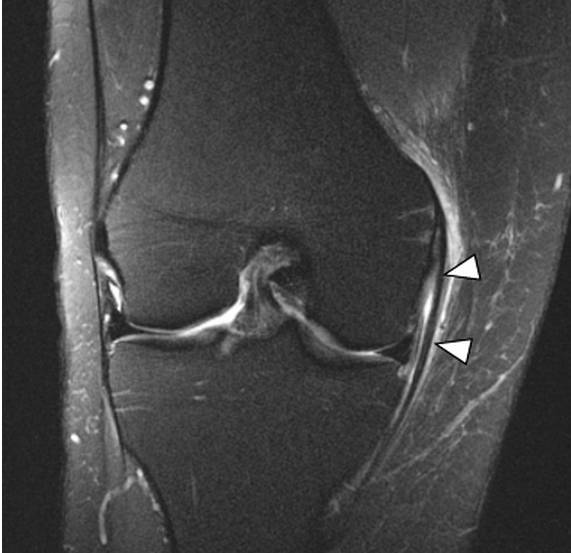

内侧副韧带损伤时MRI的典型表现包括韧带深浅两层间的滑膜囊肿胀、皮下软组织肿胀、内侧副韧带撕裂与周围血肿。韧带纤维的损伤可从单纯的排列紊乱到完全撕裂(图5~图8)。其他MRI表现有关节腔积血、股骨外侧髁或胫骨平台挫伤、半月板损伤、其他韧带损伤、以及股骨内侧髁的部分撕脱骨折(极为少见)。MRI的冠状位图像可很好地观察内侧副韧带及后内侧角。

图6,内侧副韧带I级损伤。肉眼观内侧副韧带完整,但仍可见高亮信号覆盖(箭头区域),此为撕裂的韧带纤维所导致的水肿。I级损伤中,水肿只在浅层可见,内侧副韧带粗细正常,紧贴骨皮质。